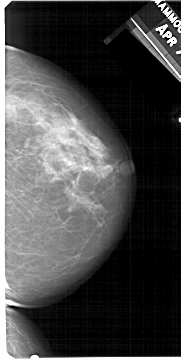

A_1512_1.LEFT_MLO

LEFT_MLO LINES 5491 PIXELS_PER_LINE 2746 BITS_PER_PIXEL 12 RESOLUTION 43.5 OVERLAY